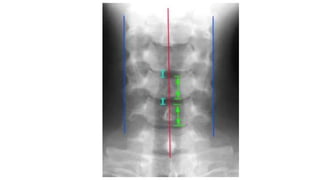

Anterior vertebral line

Posterior vertebral line

Spinal laminar line

Line across the spinous process

• #23 Ant vert body line Post vert body line Spinal laminar line Line across the spinous process

• #24 Too wide or narrow or uniform Too wide or parallel Too wide too narrow